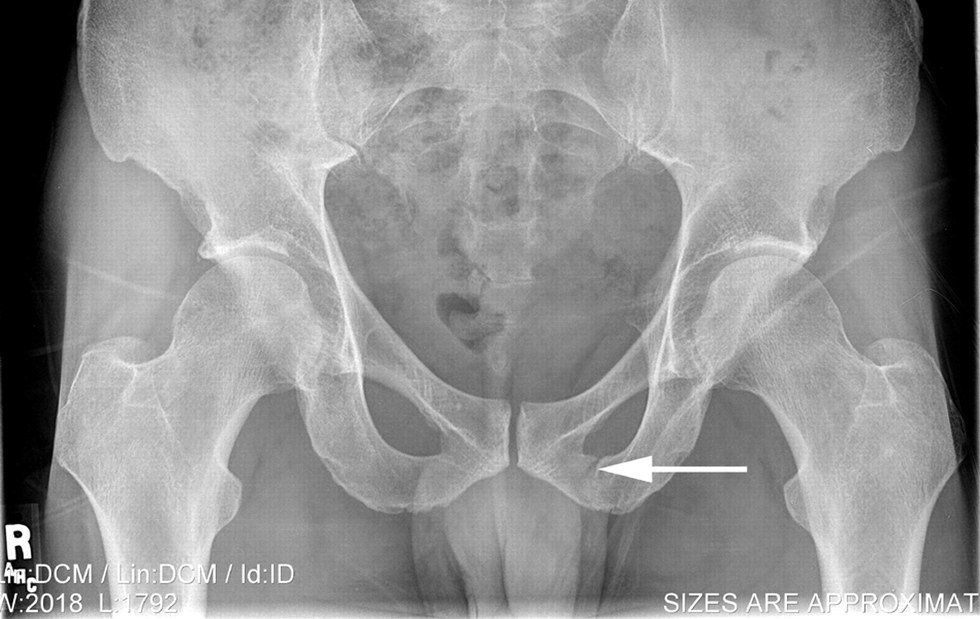

When the doctor returned, she notified me-- I had a stress fracture. It was in the inferior pubic ramus, but for simplicity merely called a pelvic stress fracture. The normal treatment for a stress fracture was “four to six weeks of no running”. I was to return again for another appointment in six weeks to check if I was okay to run again. Six weeks of lethargy and restlessness.

My doctor said I shouldn’t have run. There, another X-Ray reading scanned my injury, and while the images displayed a stress fracture that had clearly healed a lot, but hadn’t done so entirely. Every time I ran, I’d be breaking down progress. And that probably again extended the length of my recovery time. I was to return in another four weeks.

The next time I returned, I followed the same procedure-- questions, X-rays-- and waited anxiously for news. Finally, my doctor declared, my stress fracture had healed, with the broken bone replaced by new “baby bone”. I could run again-- I was supposed to go to physical therapy and take it slowly, but I could run.